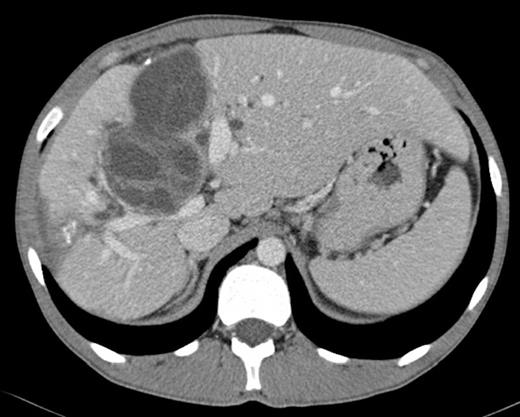

Laboratory investigations showed a slight anaemia, elevation of serum bilirrubin (conjugated 10.6 mg/dl), alkaline phosphatase (959 U/L), gamma-glutamyl transpeptidase (755 U/L). Hydatid serology was positive. Abdominal ultrasound demonstrated multiple cystic lesions spread in the liver, splenic hilum and peritoneal cavity. CT-scan confirmed the presence of numerous hydatid cysts, in different stages of development (type I-IV of Gharbi Classification), ranging from 3 to 8 cm in diameter, with 3 involving the right lobe of the liver and segment 4 (Fig.1). The splenic hilum contained a 4 cm cyst, and 9 more cysts were described in peritoneal cavity: near the gallbladder, in the root of the mesentery, in the right iliac fossa and in the Douglas pouch (Fig. 2). Cholangio pancreatography (MRCP) showed intra-hepatic bile ducts dilatation. Cholangiography (ERCP) was attempted without success. Pre-operative albendazole therapy (10 mg/Kg) was prescribed for 4 weeks.